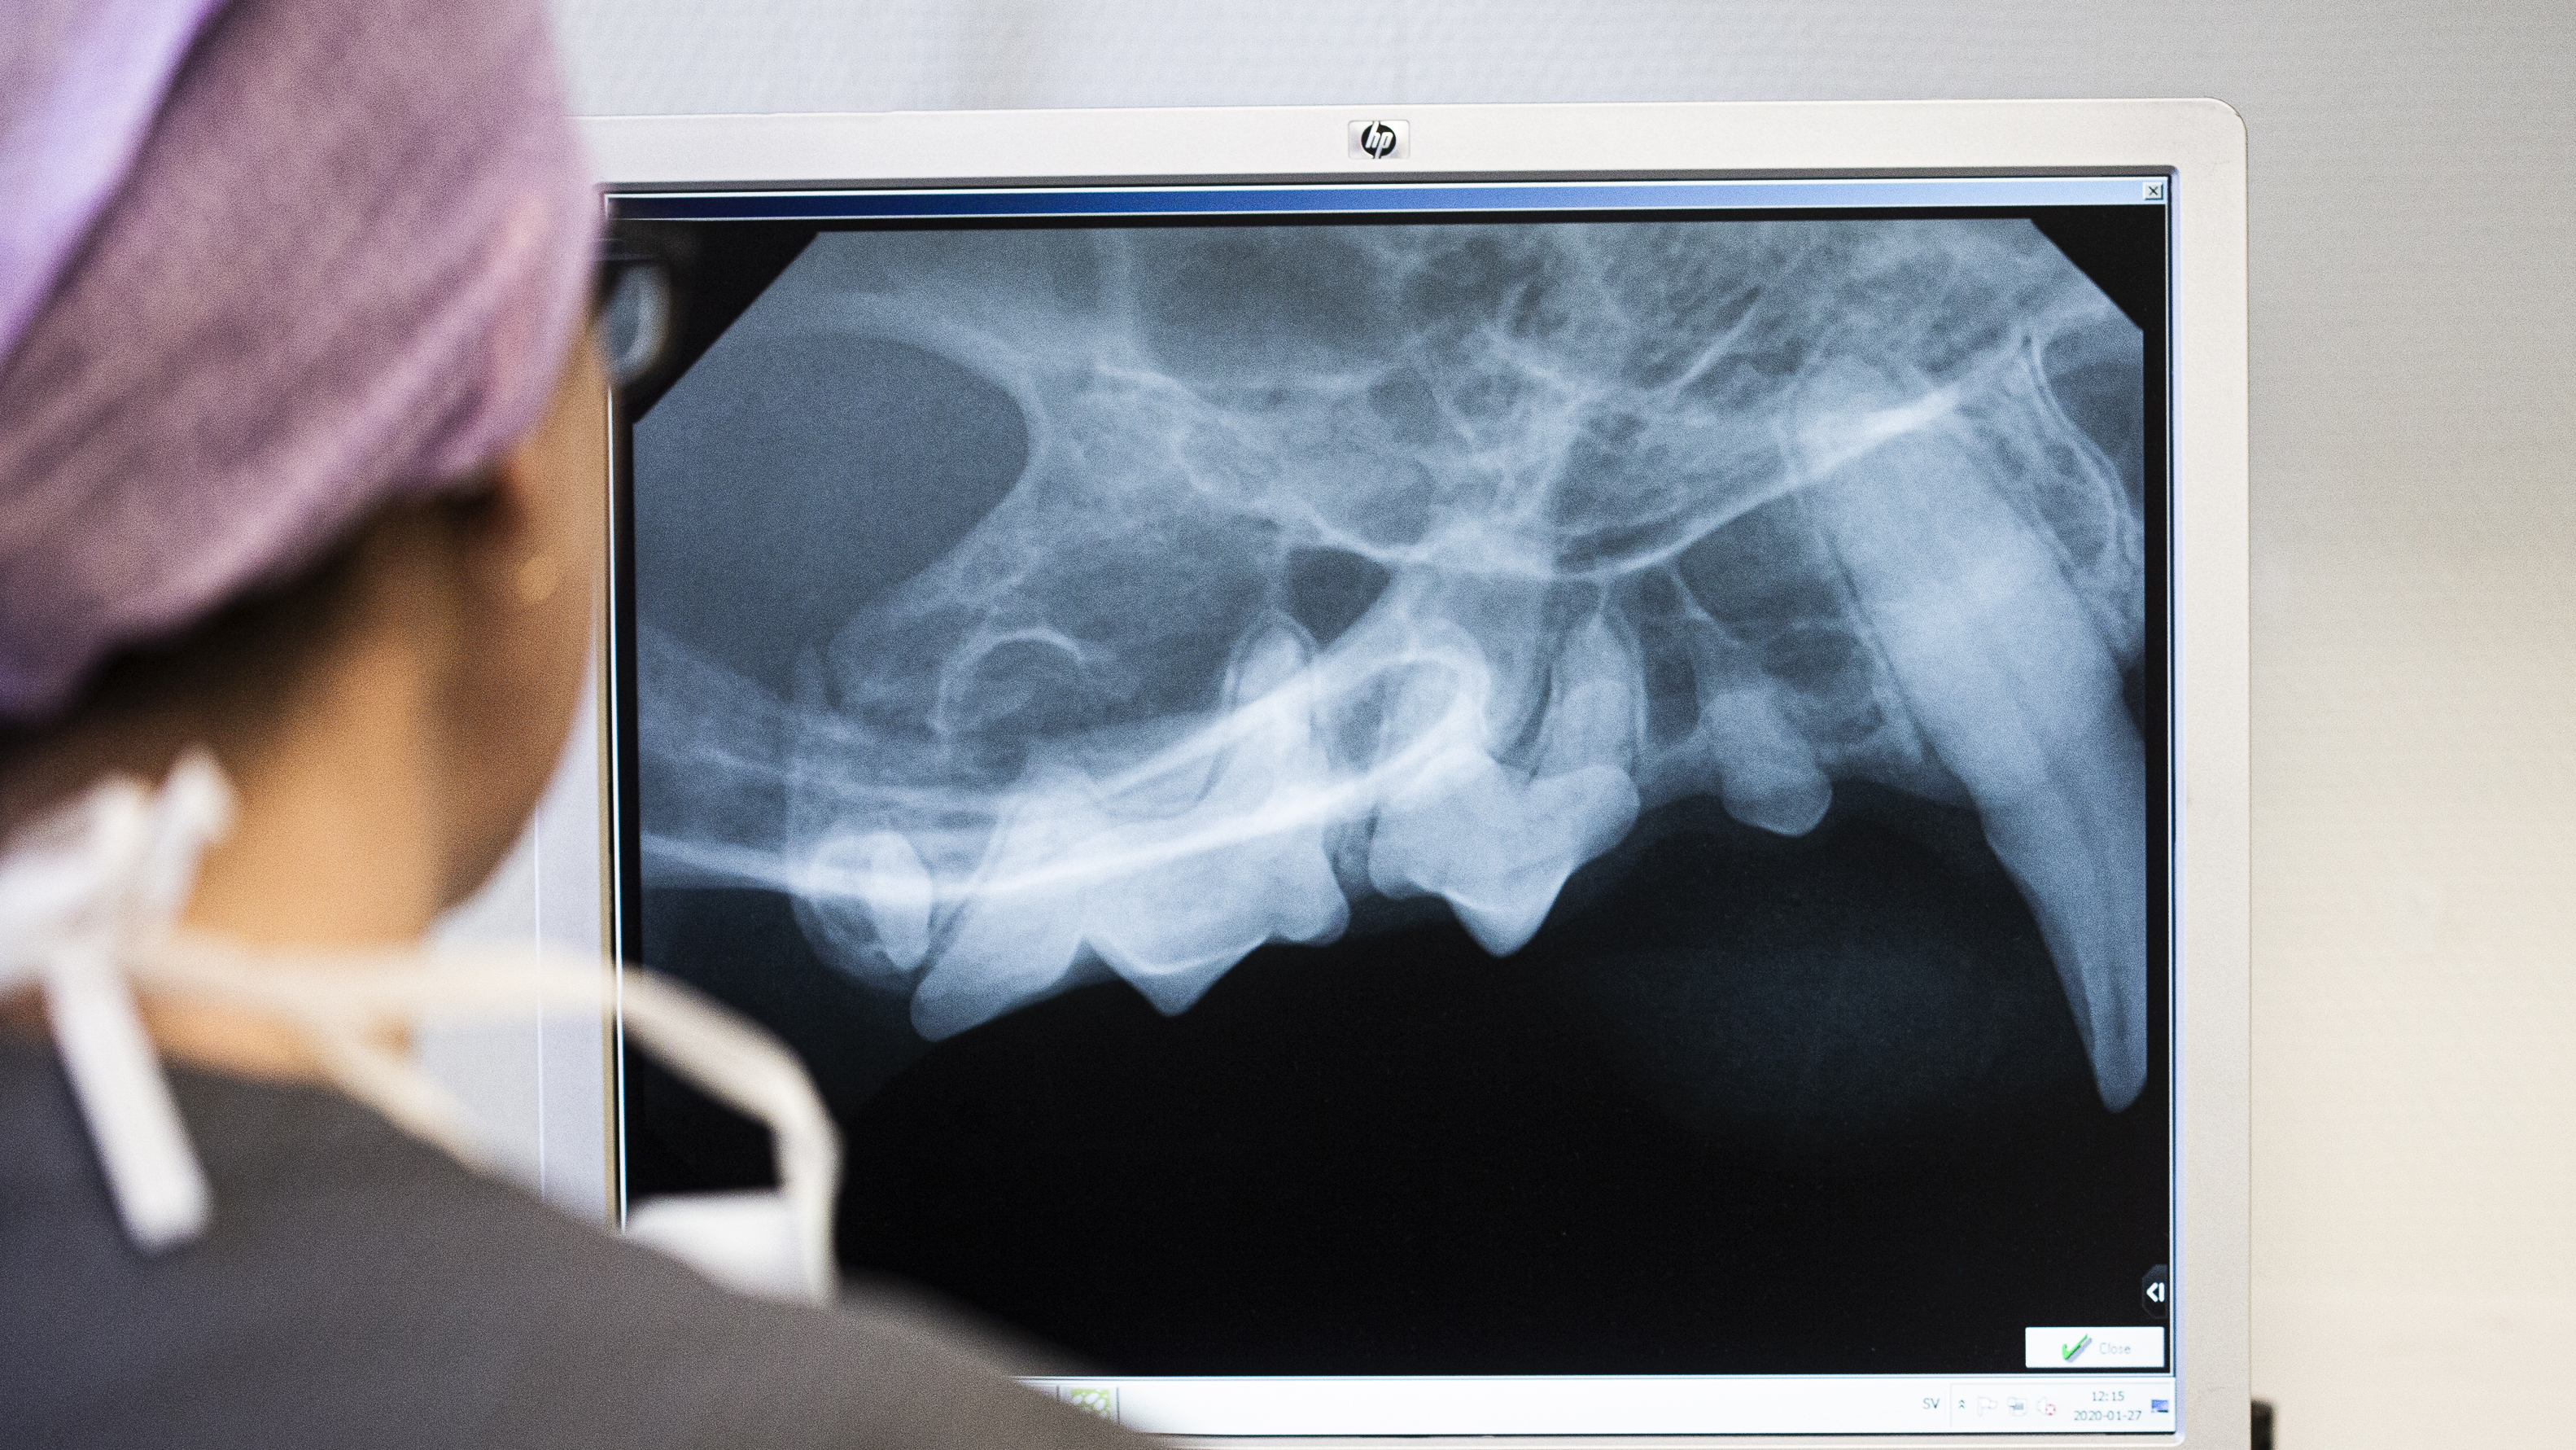

A veterinarian looks at an X-ray of teeth. Photo.

Photo: Peter Rutherhagen

Students feel unprepared for small animal dentistry

Dental problems are very common in dogs and cats, yet they are often overlooked in animal healthcare. A new study from SLU shows that both veterinary students and animal care students feel unsure about their dental skills as they approach graduation.